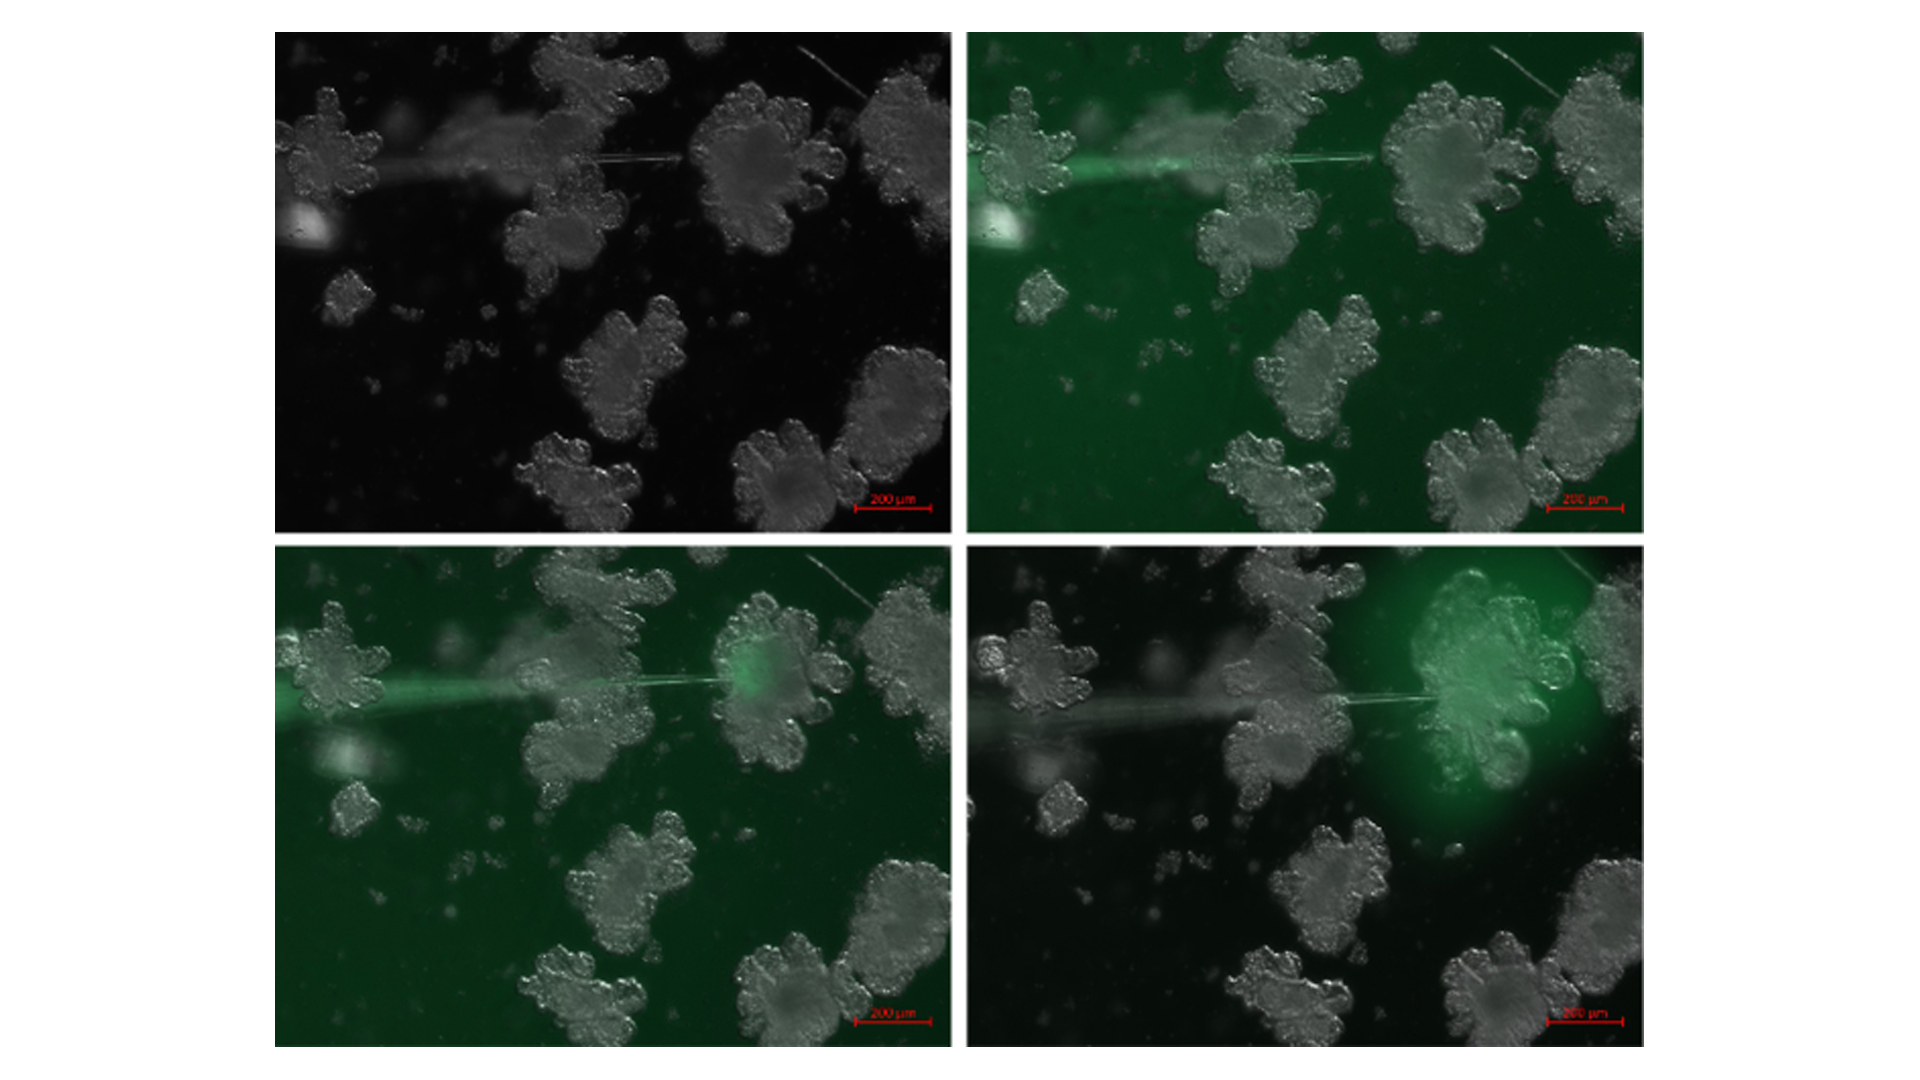

Mit einem neu entwickelten 3D-Sensorsystem entstehen hochkomplexe biologisch-technologische Schnittstellen, die es erlauben, die elektrophysiologischen Signale von komplexen kugelähnlichen Organoiden zu verfolgen und zu analysieren.

Die Promotion zielt daher darauf ab, Methoden zur Untersuchung der physiologischen Prozesse in dreidimensionalen Zellverbänden zu entwickeln, die als in-vitro-Modelle der Darmwand dienen. Hierzu werden neuartige Mikroelektrodensensorsysteme entwickelt, die in der Lage sind, sich um den Zellverband zu legen oder von den Zellen umschlossen zu werden und so eine direkte Interaktion mit den Zellen zu ermöglichen. Die Integration von Mikrokapillaren in diese Elektrodensysteme ermöglicht die gezielte Applikation von Testsubstanzen auf die künstliche Darmschleimhaut und die Überwachung der Qualität der Darmbarriere. Zur optimalen Auslegung des Elektrodennetzwerks werden Prüfstände entwickelt, die die mechanischen Eigenschaften der Darmorganoide ohne Beeinflussung der Physiologie während des Handlings präzise bestimmen können, beispielsweise deren maximale Belastbarkeit. Die Untersuchung der biomechanischen Interaktion zwischen Gewebe und Elektrode sowie die Ursachen elektromechanisch-induzierter Artefakte werden erforscht, um die Qualität der abgeleiteten Signale von Darmorganoiden mit Peristaltik zu maximieren. Des Weiteren werden Testplätze zur Elektrodencharakterisierung bezüglich Impedanzspektroskopie, Galvanik, elektrischer Feldverteilung und deren Mikrofonie entwickelt. Die Analyse des Konstruktionswerkstoffs Polyimid (PI 2610, PI 2611) beruht auf den Schwerpunkten der Biokompatibilität und der mechanischen Eigenschaften, um die Zuverlässigkeit und Funktionalität der Netzwerke in biologischen Prozessen zu gewährleisten. Aufbauend auf diesen Erkenntnissen werden die Modelle, Elektrodennetzwerke und intestinalen Organoide mittels der Finite-Elemente-Methode (FEM) evaluiert, um deren elektrisches, mechanisches und biologisches Zusammenspiel zu optimieren. Nach seiner Entwicklung wird das Elektrodennetzwerk in einer in-vitro-Testumgebung eingesetzt, und es werden damit dreidimensionale elektrophysiologische Signale erfasst. Diese Erkenntnisse können zur Entwicklung neuer diagnostischer und therapeutischer Strategien beitragen.